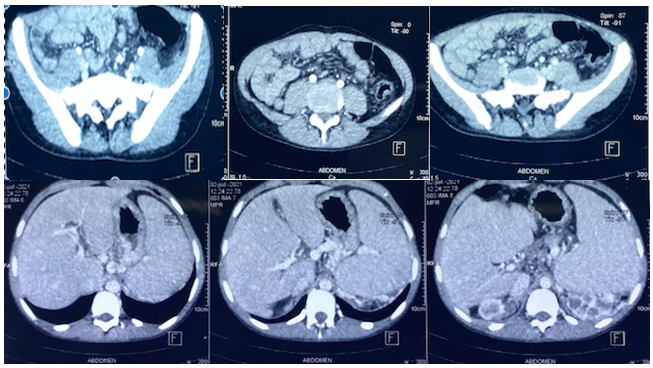

Hepatorenal Polycystosis Complicated By Hepatic Cirrhosis: A Case Report

Meryem Aouroud, Mariama Jarti, Marj Zohour Haida, Abderahmane Jallouli, Adil Ait Errami, Sofia Oubaha, Zouhour Samlani, Khadija Krati